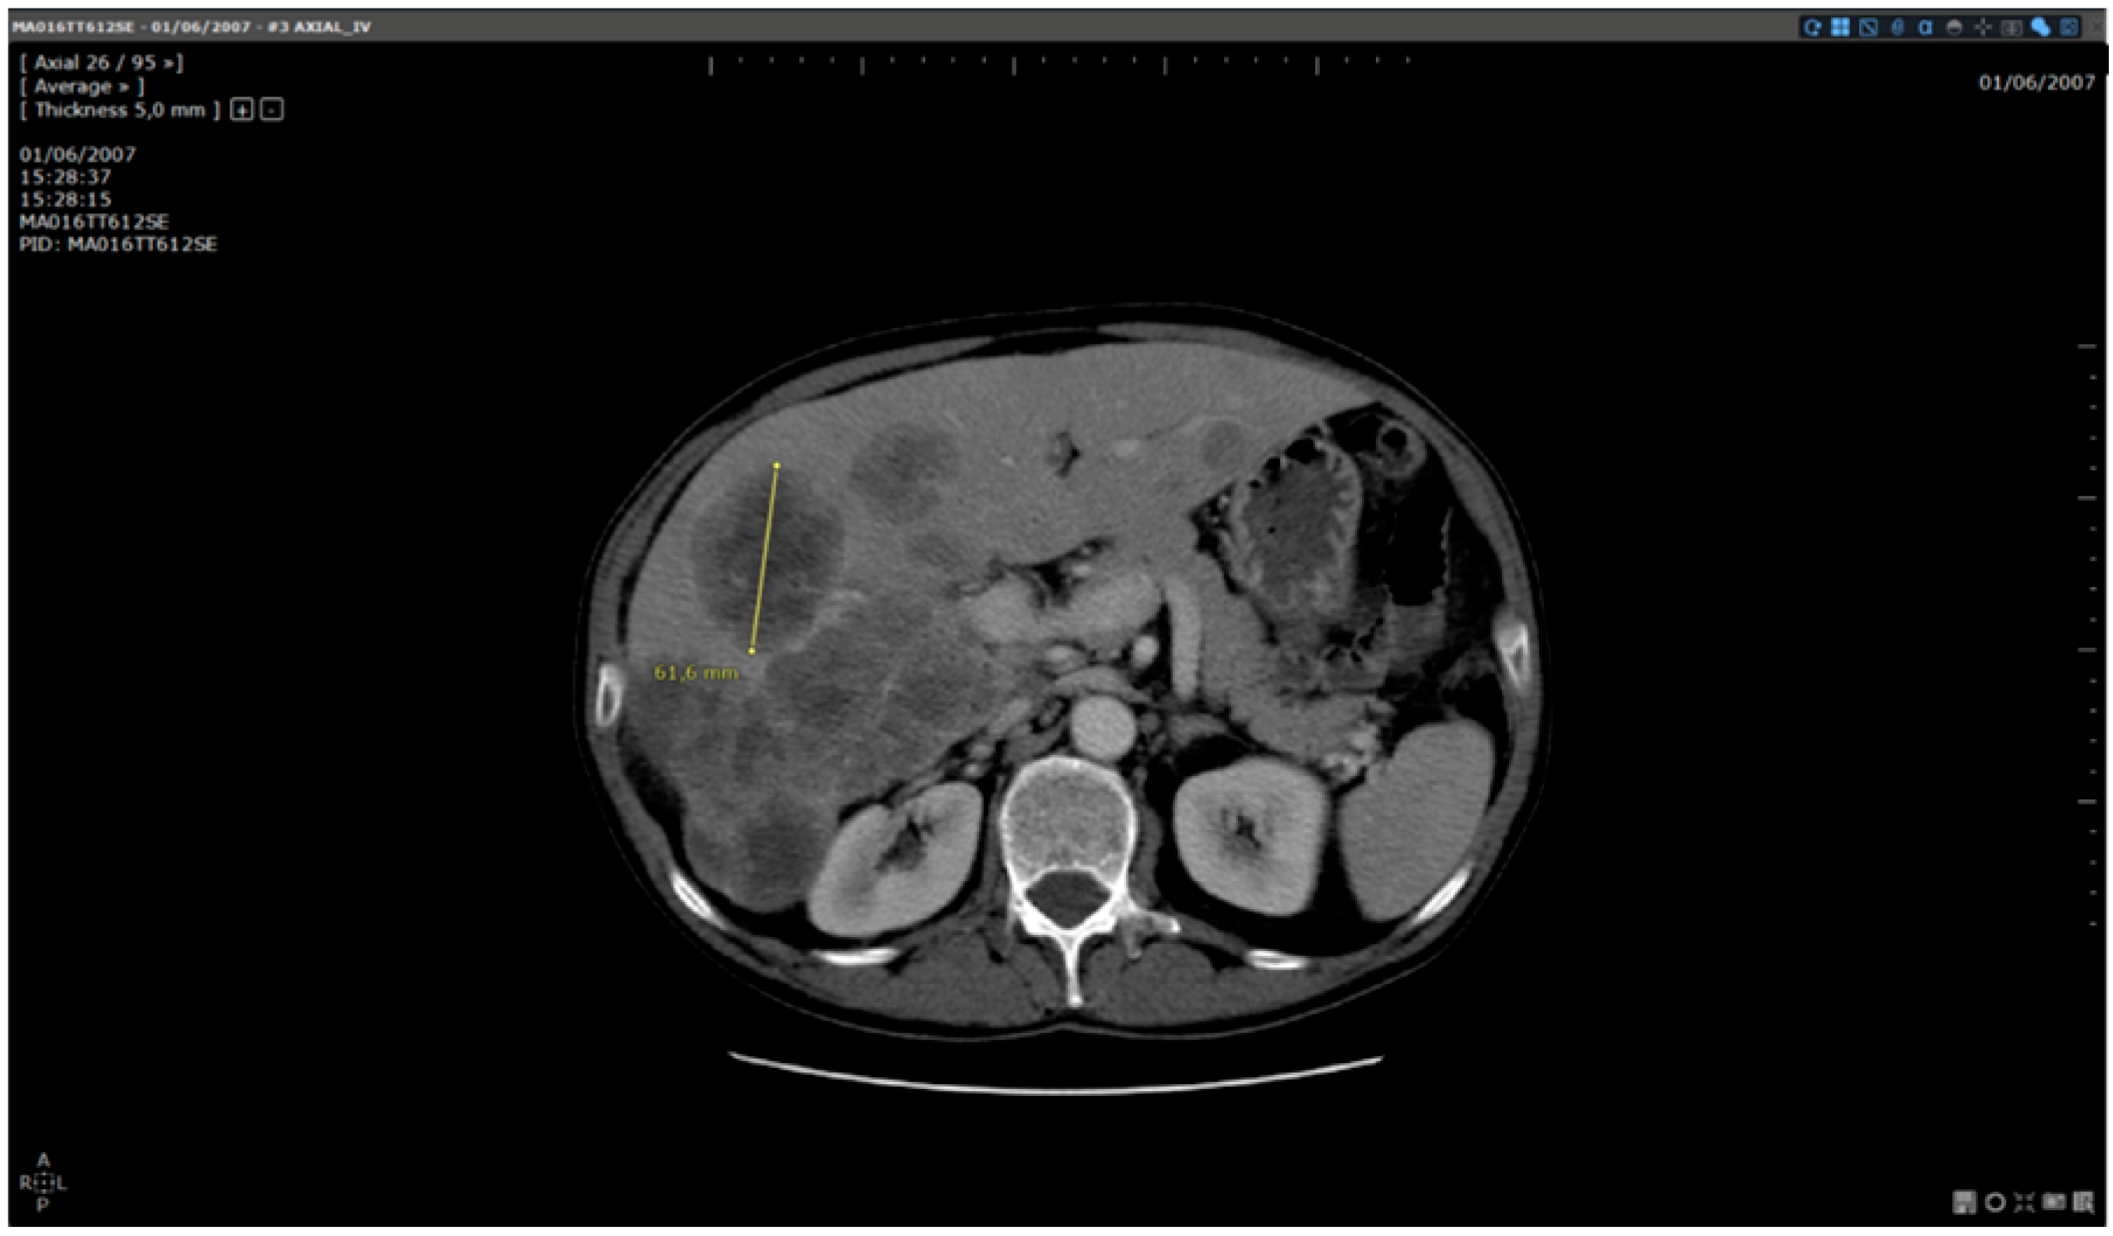

- Standard reading: Manual determination of RECIST response using a standard viewer (Myrian®, Intrasense, France) without specific options dedicated to oncologic follow ups. This reading is called “manual reading” in the rest of the article.

- Reading with dedicated software: Determination of RECIST response with the dedicated application for oncologic follow ups, Myrian® XL-Onco, with specific functionalities:

| Step 3 | Target localisation on baseline study | Manual | Automated |

| Step 4 | Target localisation on follow up study | Manual | Automated |

| Step 5 | Target measurements on follow up study | Manual | Manual |